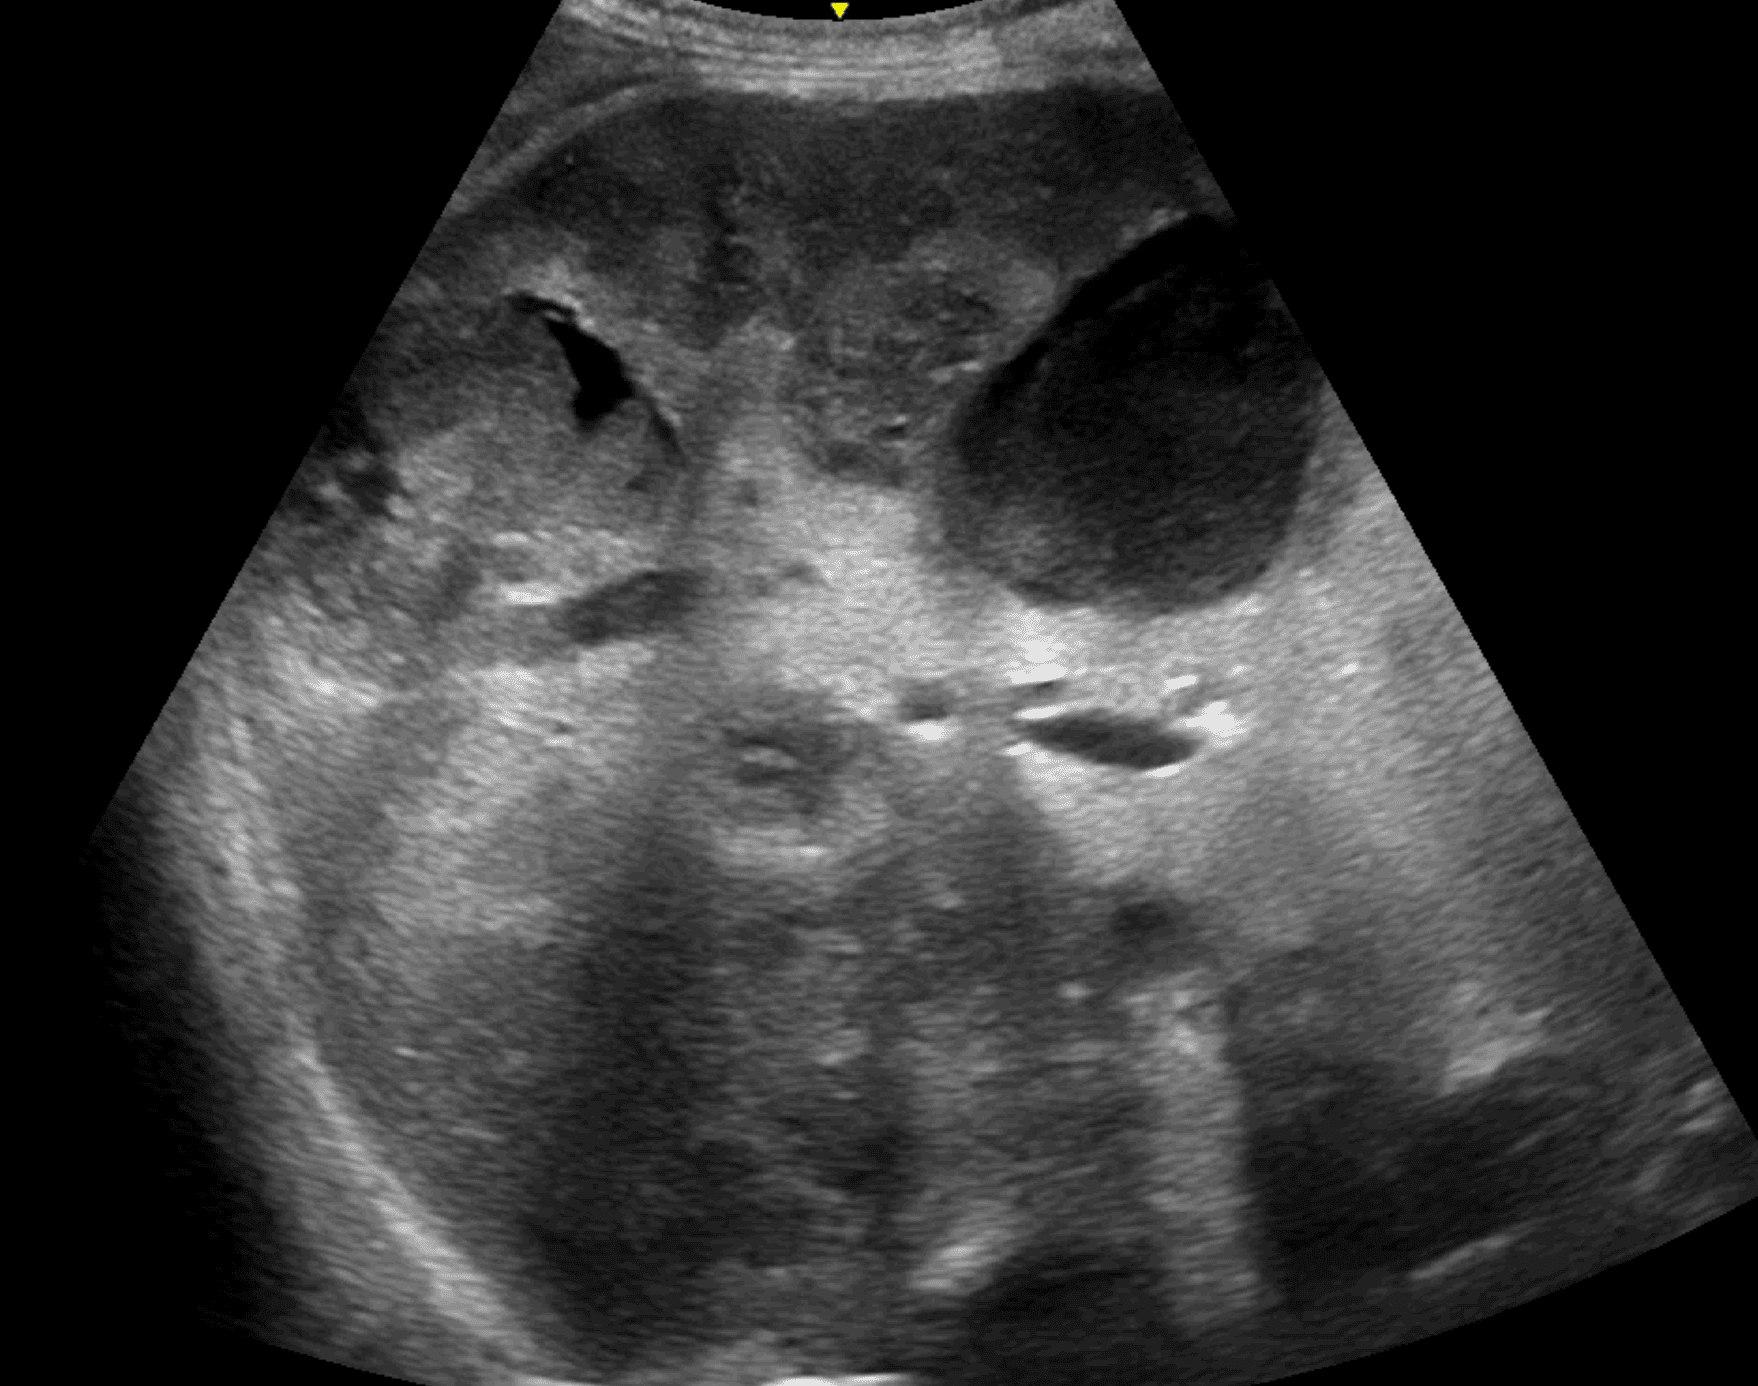

Se realiza una ecografía abdominal a pie de cama con hallazgo de múltiples imágenes hipodensas con contenido heterogéneo y áreas quísticas en hígado, sugestivas de metástasis, por lo que se solicita TAC abdominopélvico que confirma dichas lesiones con componente necrótico sobreinfectado y una con extensa neoplasia rectal localmente avanzada.

Como conclusiones me gustaría reforzar el uso de la ecografía clínica en urgencias ya que puede ser clave tanto para realizar diagnósticos que se pasarían por alto sin esta herramienta, como para acelerar procesos diagnósticos como en este caso.